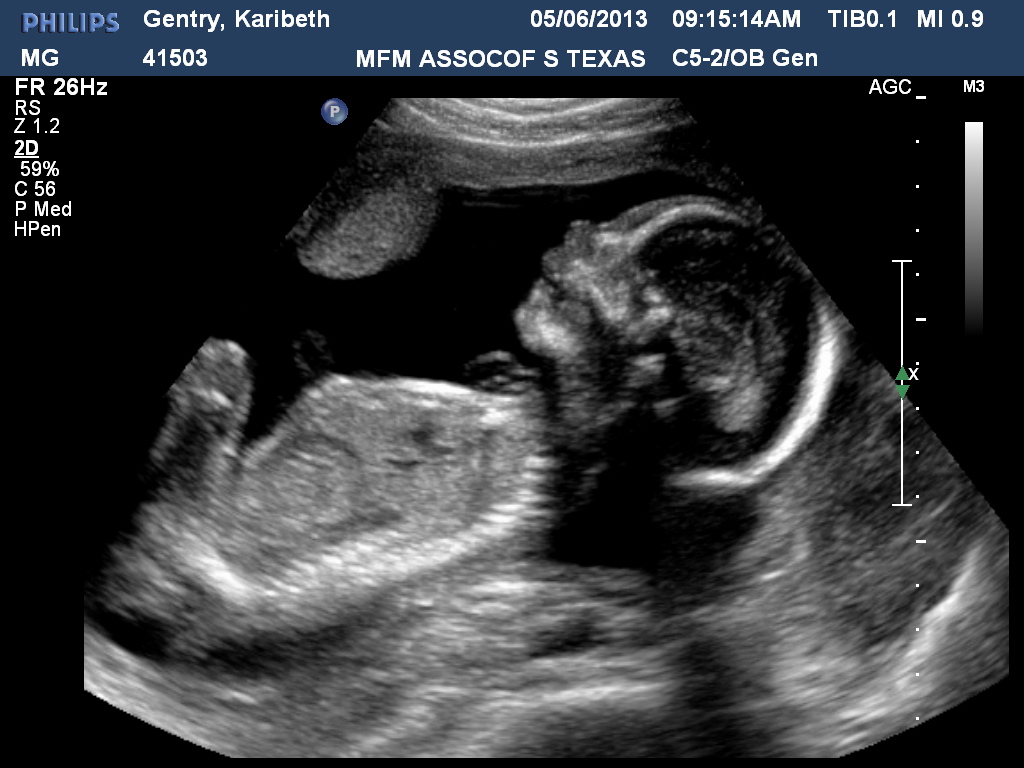

From karibethandjoshgentry.blogspot.com

The Gentry's Journey Level II Ultrasound Indications For Level 2 Ultrasound Most doctors suggest them for all pregnant women. Images are much clearer and more detailed than the fuzzy. This period represents a compromise. What exactly does a 20 week anatomy scan show? Suspected fetal anomaly during a level i examination severe. Between 18 and 22 weeks into your pregnancy, your baby will be large enough for your health care provider. Indications For Level 2 Ultrasound.